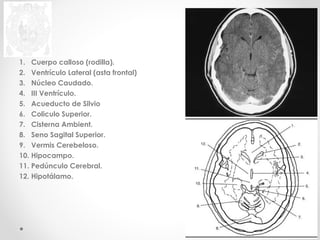

1. Cuerpo calloso (rodilla).

2. Ventrículo Lateral (asta frontal)

3. Núcleo Caudado.

4. III Ventrículo.

5. Acueducto de Silvio

6. Coliculo Superior.

7. Cisterna Ambient.

8. Seno Sagital Superior.

9. Vermis Cerebeloso.

10. Hipocampo.

11. Pedúnculo Cerebral.

12. Hipotálamo.